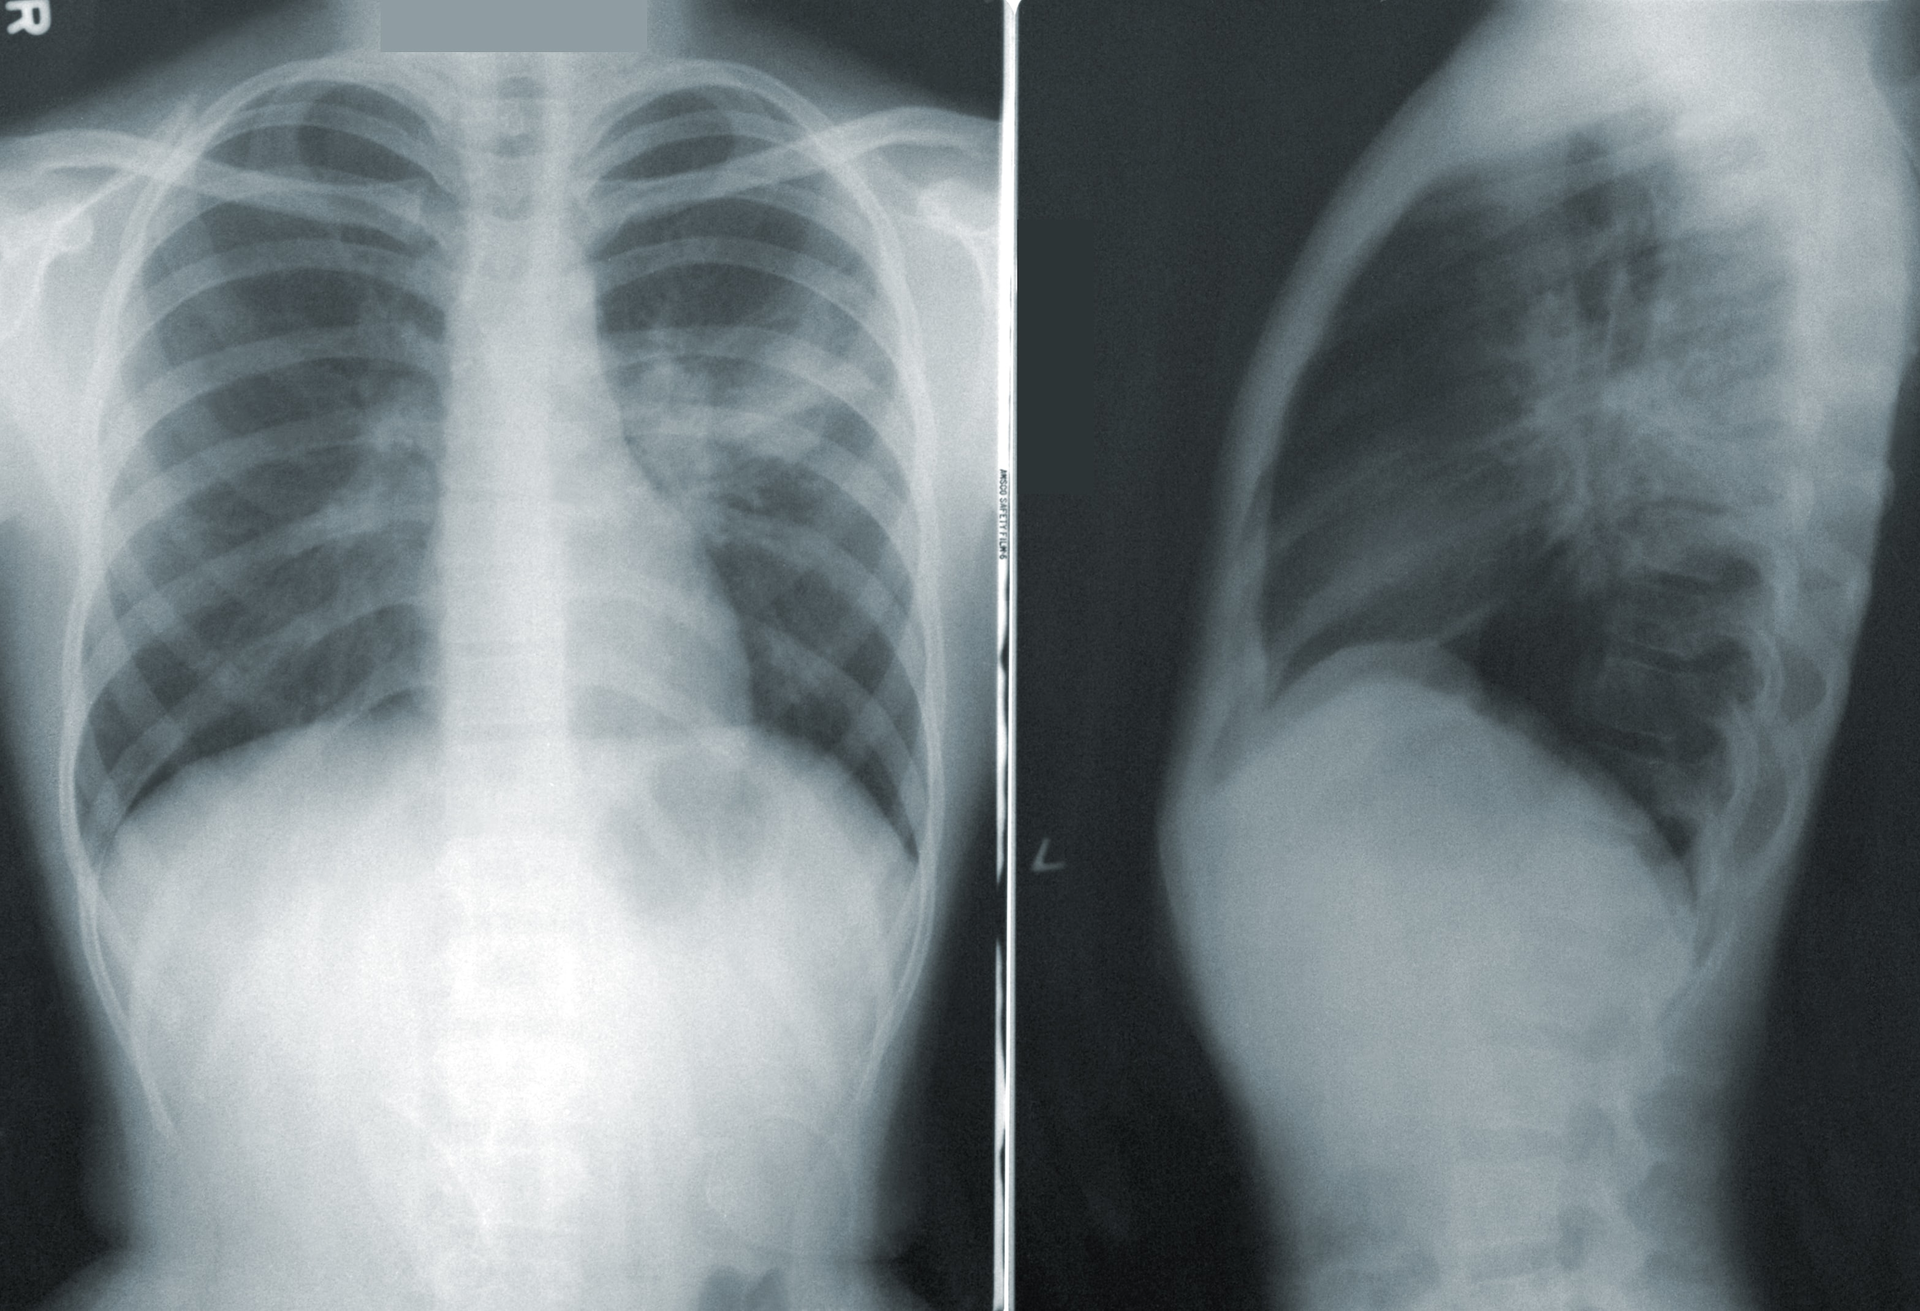

Lung cancer is the leading cause of cancer deaths worldwide. EGFR mutations are an important therapeutic target in NSCLC; EGFR Exon20 insertion mutations, specifically, are associated with resistance to immune checkpoint inhibitor therapies and poor patient prognosis. Further, EGFR Exon20 insertion mutations are often under-detected by conventional, single-gene testing methods. This is driving the need for more comprehensive biomarker testing with NGS technology, which simultaneously interrogates multiple biomarkers for early identification and appropriate characterization of cancer patient samples.